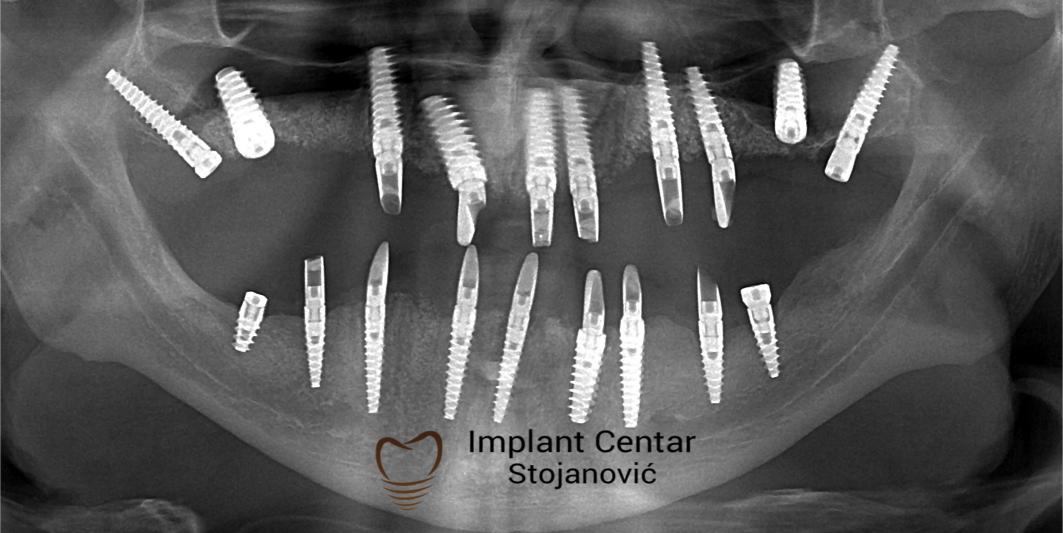

Na slici 1. i slici 2. prikazan je izgled pacijenta pre početka terapije – klinički i rendgenološki.

Nakon vađenja zuba, ugrađeni su implantati. Na slici 3 prikazan je ortopan snimak sa ugrđenim implantatima. Tokom perioda osteointegracije, pacijent je bio zbrinut fiksnim privremenim krunicama na implantatima, koje su izrađene samo dva dana nakon hirurške intervencije.

Zbog toga je plan terapije uključivao vađenje svih preostalih zuba i ugradnju implantata u gornjoj i donjoj vilici. U gornjoj vilici postavljena su i dva tuberopterigoidna implantata, kao zamena za sinus lift proceduru, što se može videti na ortopan snimku nurađenom odmah nakon ugradnje (slika 3).